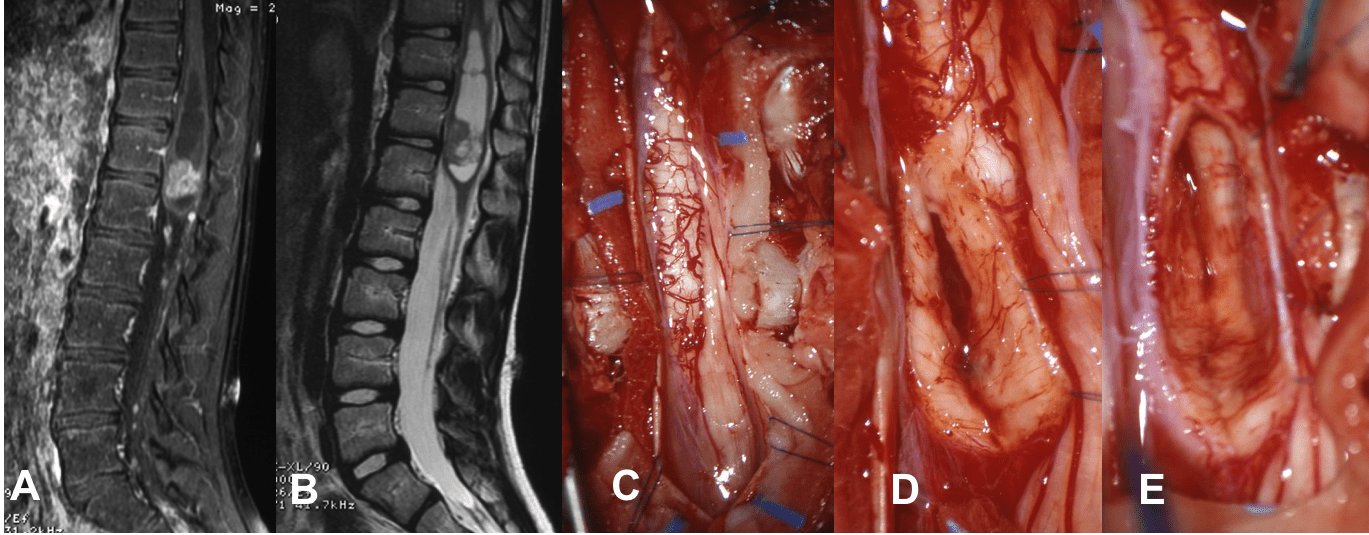

l’épendymome

pouvant être sporadique ou associé à la NF2, c’est une tumeur en règle générale centra-médullaire, extirpable par une ouverture du sillon médian postérieur (ci-dessous). l’épendymome intra-médullaire est en règle générale de grade 2, il est distinct de l’épendymome myxo-papillaire qui intéresse la queue de cheval, comme des épendymomes intra-crâniens qui ont une biologie différente.